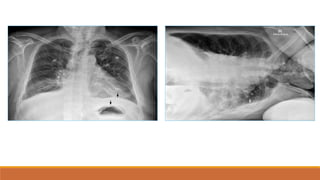

Hít đủsâu

-

‐Cung sau xương

sườn 10 nằm trên

vòm hoành (P)

Hít không đủ

sâu

‐Các mạch máu phổi

sẽ bị dồn ép lại đặc

biệt là vùng đáy phổi

Nhầm với viêm

thùy dưới phổi